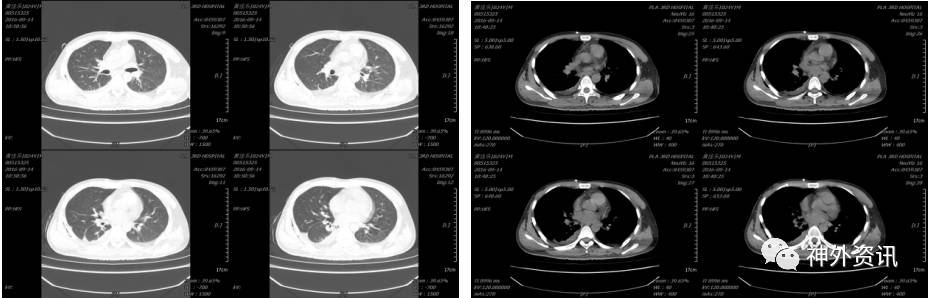

患者于2016-08-27出现发热,伴咳嗽,白细胞(WBC)16.67×109/L、中性细胞比率(NE%)87.8%、中性细胞计数(NE)14.6×109/L、降钙素原测定(PCT)0.45ng/ml、超敏C反应蛋白测定(UsCRP)35.20mg/L,给予舒普深静滴后,2016-08-30复查血常规:白细胞(WBC)6.76×109/L、中性细胞比率(NE%)57.4%、超敏C反应蛋白测定(UsCRP)4.10mg/L、降钙素原测定(PCT)0.05ng/ml,2016-09-02体温恢复正常,停用舒普深, 2016-09-10再次出现发热, 体温38.6度,患者出现腹痛,2016-09-12腹部B超及MRI示:腹腔包裹性积液、双侧胸膜腔少量积液。2016-09-13日查胸部CT示:1.双肺下叶渗出性改变伴右肺下叶部分不张,2.双侧胸膜腔积液,以右侧为著。请呼吸科、胸外科会诊后,行胸腔闭式引流,血培养未见异常,胸水生化提示感染性渗出性改变。

2016-09-12行胸部超声后,复查腹部MRI示(2016-12-12 17:46):

2016-09-13复查胸部CT示:

胸外科2016-09-13给予胸腔闭式引流,当日引出淡黄色胸水约600ml,送化验示:淡黄色浑浊胸水,白细胞手工计数1363.00×106/L、胸腹水糖(XGLU) 5.43mmol/L、胸腹水蛋白46.60、普通培养无细菌生长,考虑渗出液,肺部感染及胸腔积水。第二日复查胸部CT示(2016-12-04 10:50):

第四日复查胸部及脑CT示(2016-09-16 15:29):